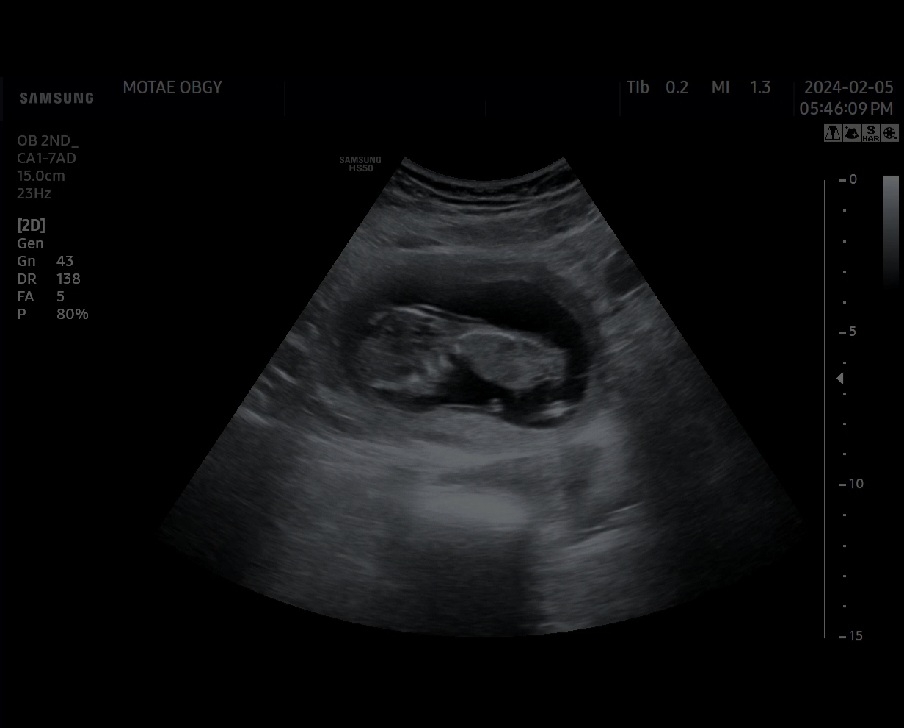

선뱔 12주 3일 각도법 성별 알수 있을까요?

성별궁금해요 고수님들